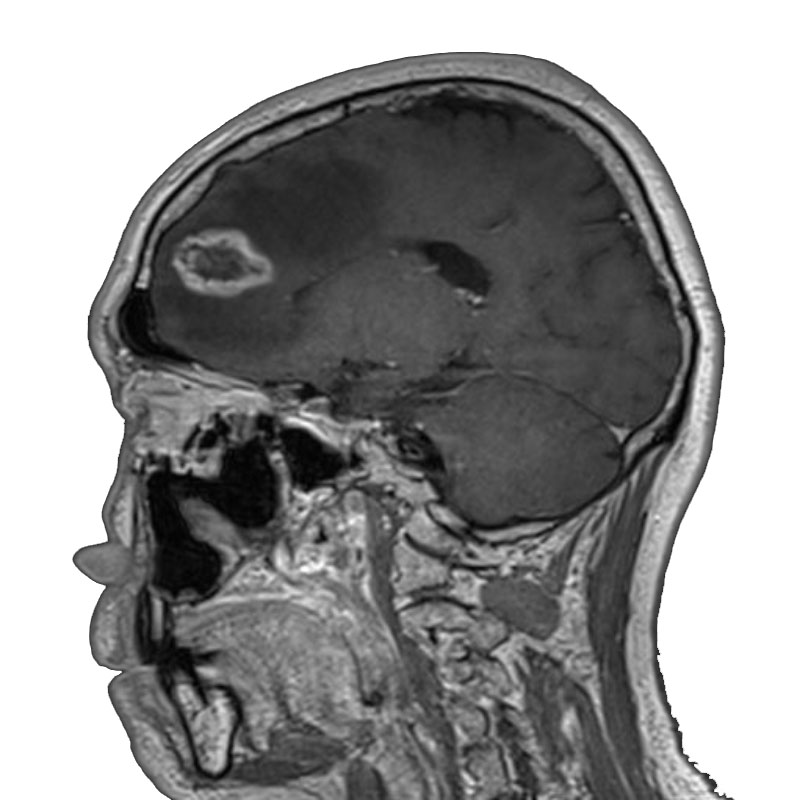

右側頭葉脳腫瘍

摘出術

南田/野本/佐伯